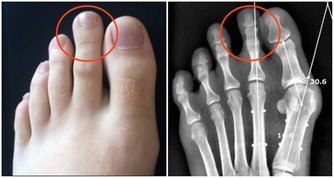

讓人容易感冒,或出現腸胃、關節不適等症狀。